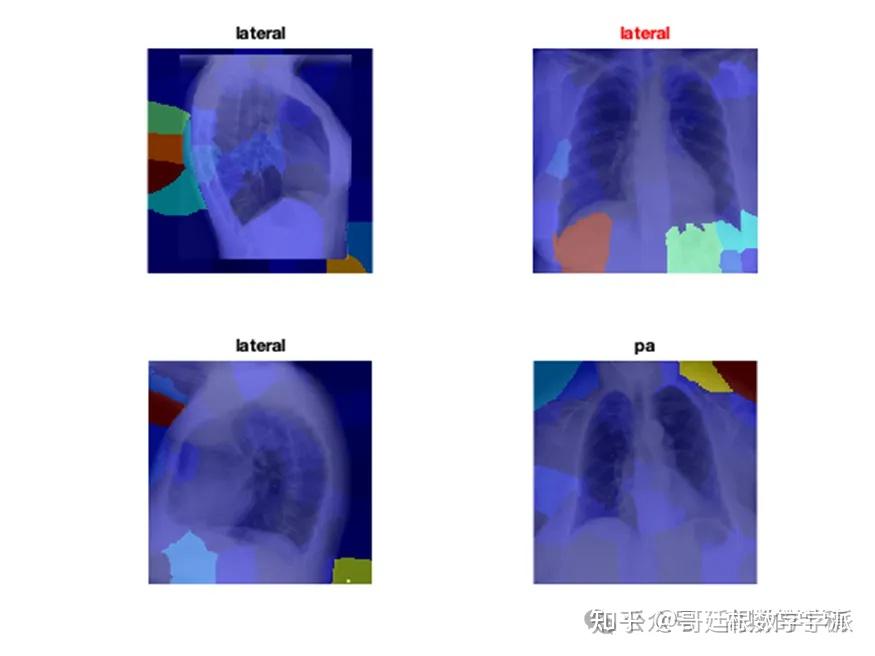

医学图像的深度学习可解释性(MATLAB R2021B)